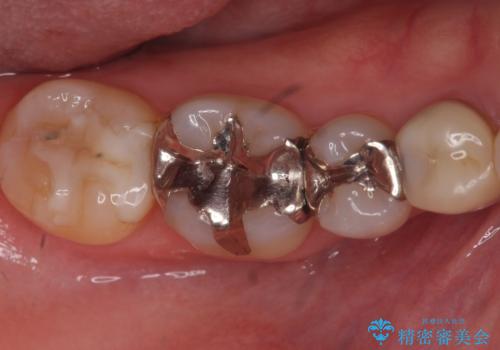

下の歯の銀歯が目立つ

- 口を開けた時、銀の詰め物が目立つとのことで来院。

拡大鏡下で詰め物を外し、う蝕がない事を確認して、セラミック(e-maxインレー)で治療を行いました。